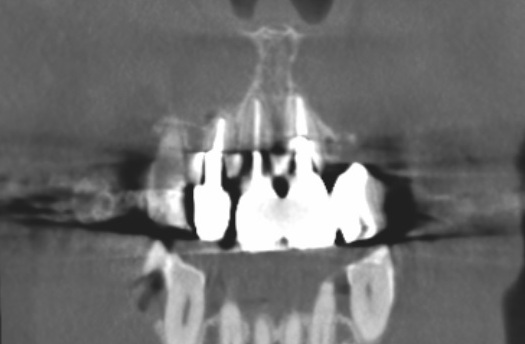

CT検査では、根の先に炎症などのトラブルはありませんでした。

もし炎症や、根の先で膿んでいる症状がある場合は、根管治療を行なう必要があります。

今回は根管治療は必要ないと判断して、かぶせ物だけをやり直すことを患者さんと相談しました。